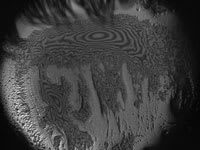

Figure 1. Interferometric analysis of tear film thinning over a silicone hydrogel lens surface |

Best photo: Can a picture speak 1,000 words? (Figure 1).

We have a lot to learn about the interaction among the lens surface, tear film thinning, evaporation and symptoms. The future will hold specific solution/ lens pairings to maximize tear film stabilization and comfort.